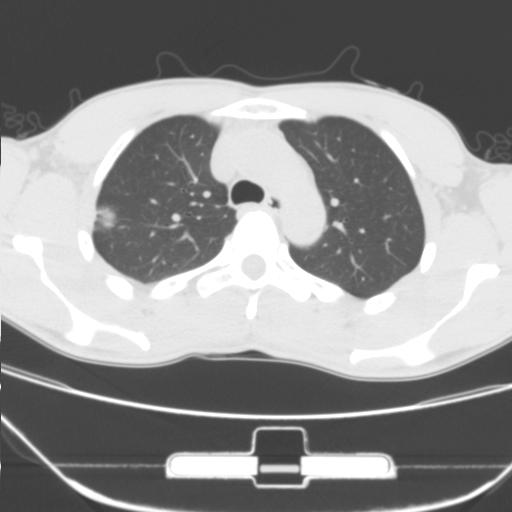

车祸伤者

右肺上叶后段近胸膜下结节样异常密度灶,似见分页及毛刺,考虑右肺上叶周围型肺ca,建议穿刺病理检查

周围型肺ca与炎性假瘤待鉴别。建议穿刺病理检查

考虑周围型肺癌

考虑周围型肺癌可能性大,建议穿刺病理检查

缺乏病史,症状体征,但这个孤立结节具备了几乎所有的恶性征象:分叶,毛刺,空泡征,胸膜凹陷征,血管集束。

考虑右肺上叶后段周围型肺癌。